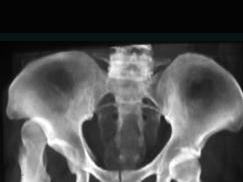

问题 女,19岁,跛行19年,请结合影像学检查,选出最可能的诊断 ( )

选项 A、髋臼骨折 B、股骨头缺血坏死 C、先天性髋内翻 D、骨盆骨折 E、先天性髋关节脱位

答案 E